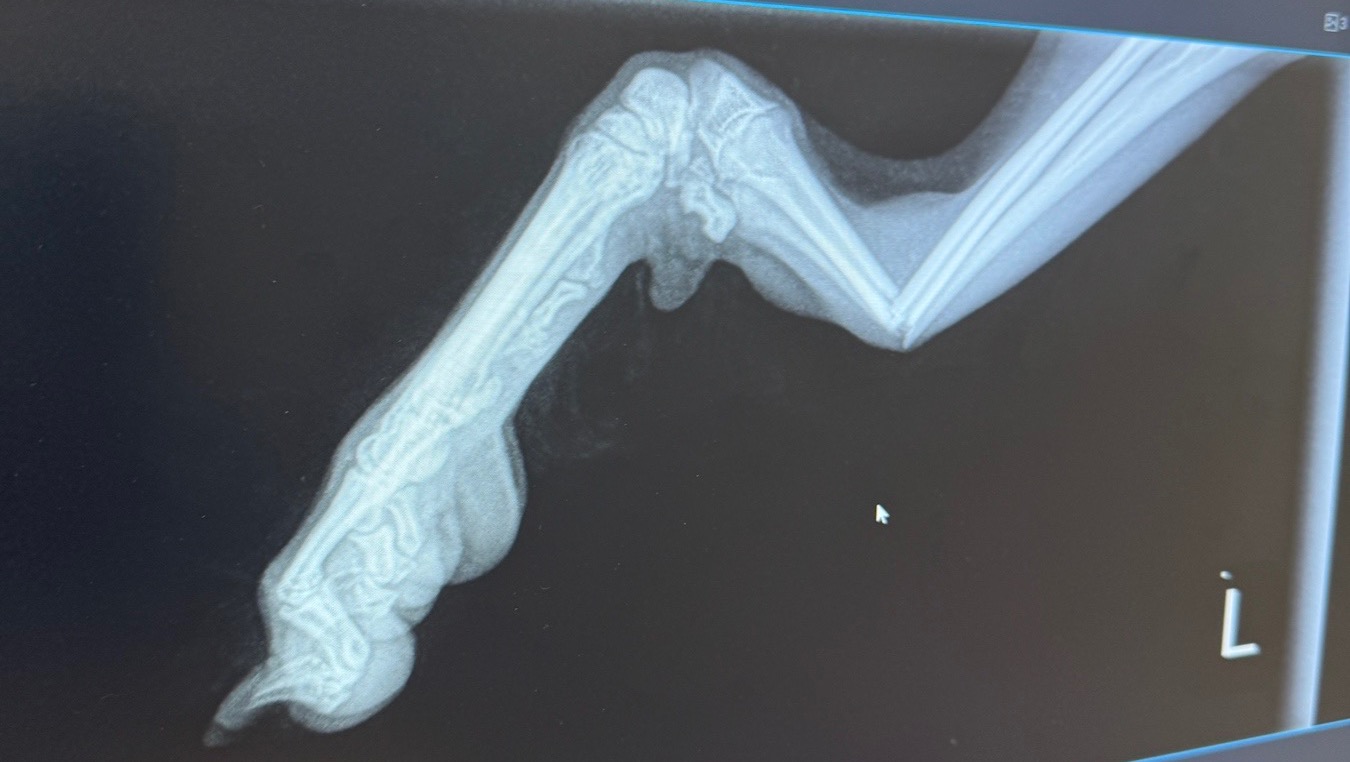

Not long ago, he broke his right leg — we fought hard for his recovery, and only recently had his bandage removed. His leg is still weak and needs careful rehabilitation.

Unfortunately, another tragedy has happened — Bobby has now broken his other leg.

He can barely walk, he is in a lot of pain, and cries and whines almost constantly. Without urgent surgery, he won’t be able to recover.

For now, to stabilize his condition while we wait for surgery, the doctors have placed a temporary bandage on his injured leg. But this is not a permanent solution — he needs surgery as soon as possible to heal properly and avoid further complications.

All medical documents and files are attached below.